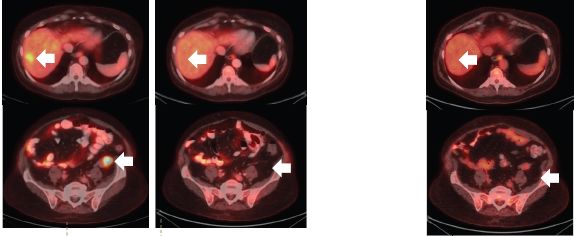

患者二:TPR-NTRK1融合非小细胞肺癌的持久反应

28岁男性被诊断为IV期NSCLC,伴有神经内分泌功能的腺癌,有脑和骨转移。

先前用顺铂和依托泊苷治疗,由于疾病进展(PD)而停药,随后进行放疗,疾病稳定。

FoundationOne检测发现NTRK融合基因,在开始使用larotrectinib后,患者在第29天时,咳嗽和背痛症状的显着改善,反应持续时间为8.21个月。